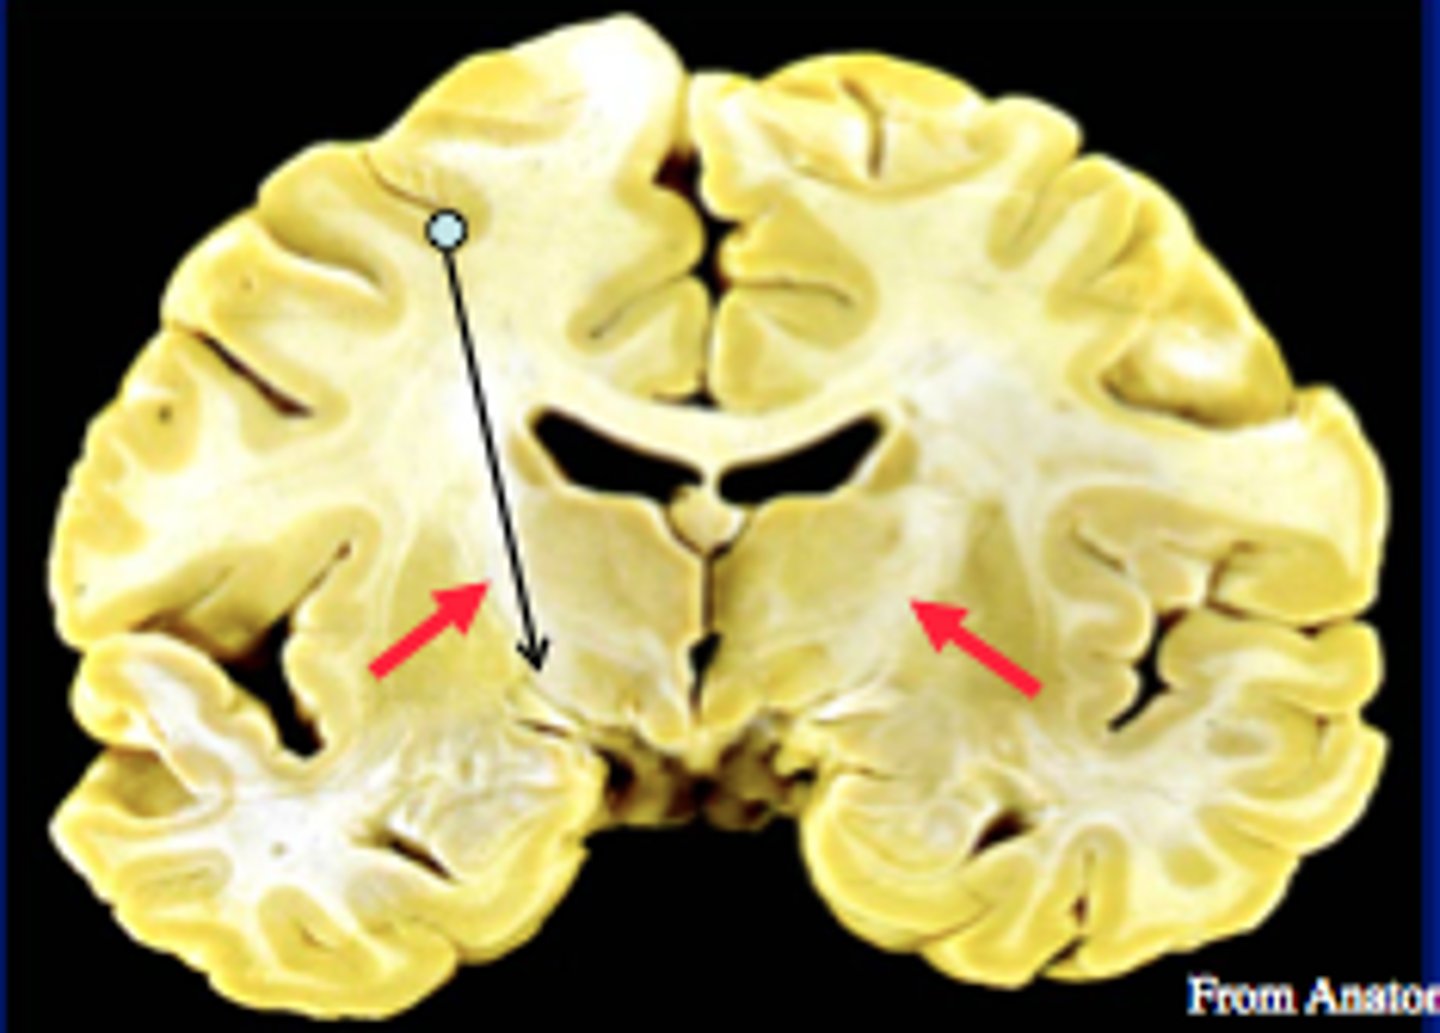

Internal Capsule

A large collection of axons that connects the telencephalon with the diencephalon

Pyramidal tracts, among other things, pass through here

Corona Radiata

All the fibers connecting cortical and subcortical regions also pass through here

Pyramidal System

The motor system that includes neurons within the cerebral cortex and their axons, which form the pyramidal tract.

Originates from neurons in the primary motor cortex, premotor cortex, supplementary motor cortex, and somatosensory cortex